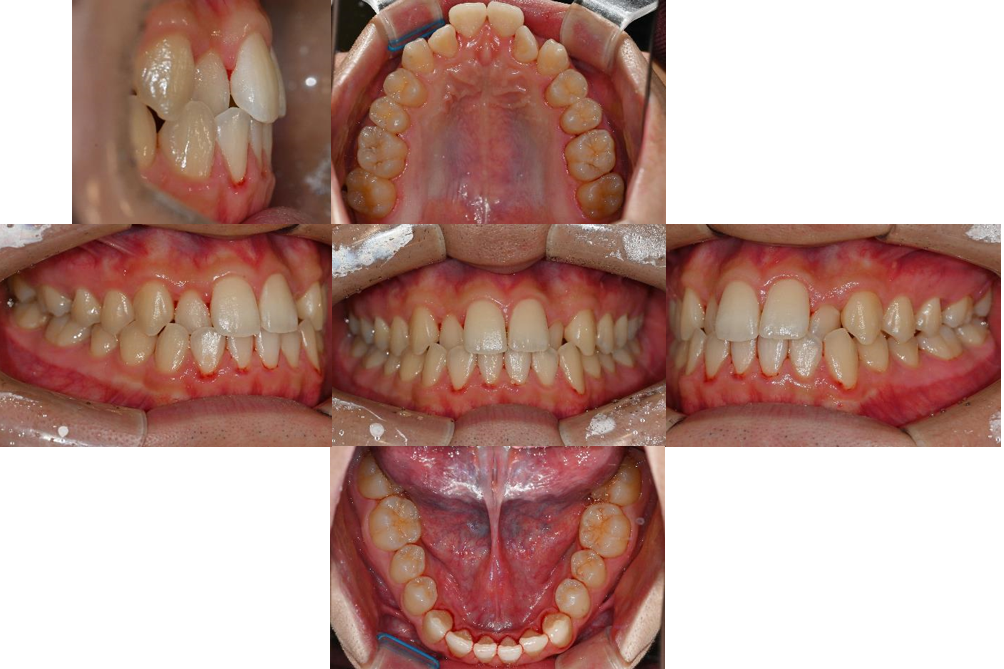

위 예시 사진을 보면 전후방적으로 위턱에 비해 아래턱이 큰 모습이죠?

바로, 전후방적으로 위턱에 비해 아래턱이 큰 골격적 특징 때문입니다.

치열 분석에서도 여러 가지 복합적인 문제들이 발견되었습니다.

가장 눈에 띄는 문제는 위 앞니가 삐뚤빼뚤하며 위아래 측절치가 거꾸로 교합되는 앞니 반대교합이었습니다.

정상적인 교합에서는 위 앞니가 아래 앞니를 2-3mm 정도 덮어야 하는데, 이 환자분의 경우 위 앞니가 아래 앞니를 덮는 양이 현저히 부족했습니다.

구치부 관계에서도 양측 모두 3급 부정교합을 보였으며, 이는 전체적인 교합 관계의 부조화를 의미합니다.

특히 주목할 점은 골격에 대해 상악 치아는 전방으로, 하악 치아는 후방으로 기울어져 있다는 것입니다.

이는 부정교합을 보상(compensation)하려는 자연스러운 적응 과정에서 나타난 변화로, 실제 골격적 부조화가 치아 경사도에 의해 어느 정도 가려져 있음을 시사합니다.

또한 위어금니 간 폭경과 아래 어금니 간 폭경의 비율에서도 부조화가 관찰되었습니다.